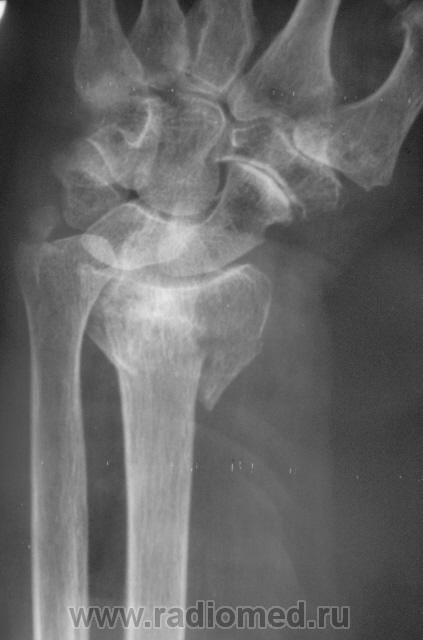

Случай 3. Пациент направлен врачом хирургом на рентгенографию лучезапястного сустава.